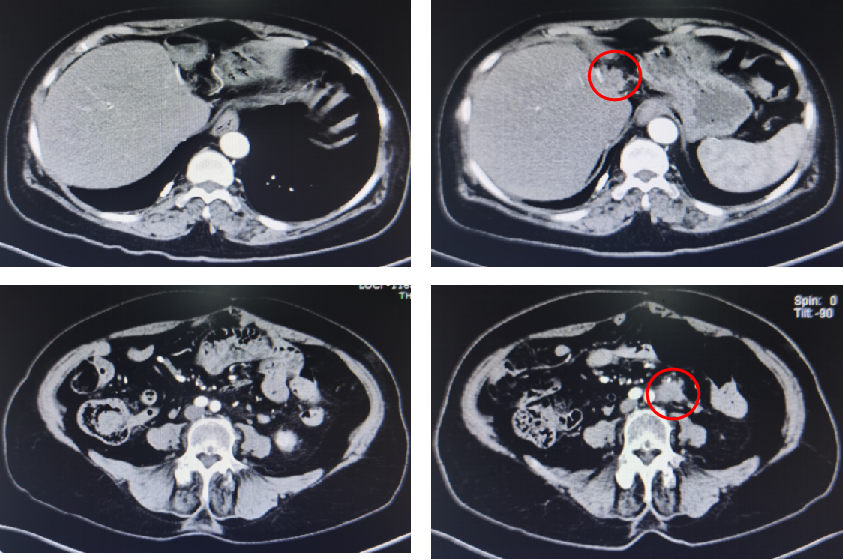

基本信息:性别 女,年龄 78岁,身高 159cm,体重 62kg。 主诉:结肠癌及肝转移瘤术后2年6个月(首次就诊时间为2018-09-10)。 既往史、个人史:“2型糖尿病”20年,予“二甲双胍 0.5g 口服 2次/日、门冬胰岛素注射液皮下注射,早 30U,晚 28U;甘精胰岛素皮下注射 20U ”降糖治疗,血糖控制一般。 家族史:无特殊。 02 初诊病史 体格检查、B超、CT及其他辅助检查。 体表面积1.60m,体格检查:浅表淋巴结未及肿大,双肺呼吸音粗,未闻及干湿性啰音,心律规整,未闻及杂音,腹壁可见陈旧性手术瘢痕,愈合良好,腹软,未及肿物,无压痛,肛查-,双下肢无水肿,起病隐匿,体检行腹部超声发现肝脏占位。 肠镜(2016-3-12):乙状结肠肿物。 咬检病理:(乙状结肠)腺癌。 肝胆胰增强CT(2016-3-10):肝左叶占位。 考虑:乙状结肠癌Ⅳ期 肝转移。 2016-3-21 于外院行“乙状结肠癌根治术+肝左叶转移瘤切除术”,术中予输血治疗,术后恢复慢,切口延期愈合。 术后病理:结肠中分化腺癌伴坏死形成,大者3.5cm×3.2cm×0.5cm,癌组织侵及浆膜脂肪层,脉管内癌栓形成,小者1cm×1cm×0.5cm,癌组织侵及粘膜下层。肠壁周围淋巴结癌转移(3/6),T3N1M1。(肝左叶)肝脏转移性腺癌伴大片坏死形成,大小6.6cm×6cm×4.5cm,结肠来源,残端及吻合口上下缘肠壁未见肿瘤侵及。 基因检测:KRAS、NRAS、BRAF 均未见突变。 初步诊断:乙状结肠癌Ⅳ期(pT3N1M1),同时性肝转移,中分化腺癌,2型糖尿病。 03 治疗方案 2016-4 XELOX 方案化疗1周期(具体剂量不详)因不良反应较重,未完成术后辅助治疗疗程。未予后续治疗,定期复查,病情稳定 胸腹CT(2017-3-19 ):右肺下叶新结节,考虑转移;肝左外叶转移瘤切除术后改变。 2017-4-1 于外院行局部肺肿物射频消融术,无治疗反应,恢复良好。 胸CT(2017-12-5):肺部新发结节,考虑转移。 【一线治疗方案(2017-12至2018-9)】 卡培他滨 1.5g po d1-14 q3w,共10个周期。 不良反应:1度消化道反应。 期间疗效评价:SD。 胸腹增强CT(2018-9-11):符合结肠癌切除术后,肝左叶切除后改变,双肺多发结节,部分较前增大。 2017-12-5 2018-9-11 建议调整方案治疗,患者家属拒绝,继续口服卡培他滨至2019年3月。 疗效评估: ECOG PS评分1分,新发活动后胸闷、气短症状 胸腹平扫CT(2019-3-26):双肺多发结节,较前增大;肝左外叶转移瘤切除术后改变。 2018-9-11 2019-3-26 评估PD。 【二线治疗方案(2019-4至2020-5)】 贝伐珠单抗 300mg ivgtt d0(体重62kg); 卡培他滨 1.5g po d1-14 q3w,共15周期。 不良反应:1级高血压、1度消化道反应。 疗效评估: 胸腹CT(2020-5-21):符合结肠癌术后、肝左叶切除术后,肝左切缘旁异常密度灶,左髂总动脉旁淋巴结;双肺多发结节,部分较前增大,右肺门肿物较前增大。 疗效评价:PD。 【三线治疗方案(2020-5至2020-10)】 西妥昔单抗 600mg ivgtt d0(体表面积1.66 m2); 亚叶酸钙 500mg ivgtt d1; 氟尿嘧啶 500mg ivgtt ,随后3500mg iv泵入 q2w,共9周期。 不良反应:无皮疹、腹泻、恶心、呕吐等。 疗效评估: 胸腹平扫CT(2020-09-07):右肺下叶背段软组织肿块,较前略减小,双肺多发小结节,转移瘤,同前;结肠癌术后、肝左叶切除术后改变,肝左切缘旁异常密度灶同前相仿,腹膜后左侧髂总动脉旁淋巴结同前。 2020-7-23 2020-9-7 疗效评价:SD(缩小趋势)。 胸腹平扫CT(2020-10-24):右肺下叶背段软组织肿块,较前(2020-9-7)略减小,双肺多发小结节,转移瘤,部分较前减小,结肠癌术后、肝左叶切除术后改变,肝左切缘旁异常密度灶同前相仿,腹膜后左侧髂总动脉旁淋巴结同前。 2020-9-7 2020-10-24 疗效评价:SD(缩小趋势)。 胸腹平扫CT(2020-12-13):右肺下叶背段软组织肿块,较前(2020-10-24)未见著变,双肺多发小结节,转移瘤,较前未见著变,结肠癌术后、肝左叶切除术后改变,肝左切缘旁异常密度灶同前相仿,腹膜后左侧髂总动脉旁淋巴结同前。 2020-12-13 疗效评价:SD。 患者未规律返院行西妥昔单抗维持治疗。 胸腹增强CT(2021-1-5):右肺下叶背段软组织肿块,较前(2020-12-13)增大,双肺多发小结节,转移瘤,左肺尖结节较前增大,余未见著变,左侧髂总动脉旁淋巴结较前增大。 疗效评价:PD。 【四线治疗方案(2021-1至2021-10)】 安罗替尼 8mg po 1次/日 d1-14 (2021-3 起因高血压2级,药物控制不佳调整为8mg qod ); 卡培他滨 1g po 2次/日 d1-14 q3w (2021-4 起因乏力2级不能耐受停服)。 不良反应:2级高血压,2级乏力,1级胆红素升高,1度消化道反应。 疗效评估: 胸腹增强CT(2021-10-3):右肺下叶背段占位,考虑恶性肿瘤,较前增大,双肺多发转移瘤,部分较前略增大,结肠癌术后、直肠区肠管明显扩张,肝左叶切除术后改变,切缘旁占位伴肝内胆管扩张,累及胆总管,考虑恶性病变,较前增大,腹膜后左侧髂总动脉旁淋巴结,较前增大,累及左侧输尿管伴以上输尿管及肾盂扩张。 2021-10-3 疗效评价:PD。 疗效评估: 胸腹增强CT(2021-10-3):右肺下叶背段占位,考虑恶性肿瘤,较前增大,双肺多发转移瘤,部分较前略增大,结肠癌术后、直肠区肠管明显扩张,肝左叶切除术后改变,切缘旁占位伴肝内胆管扩张,累及胆总管,考虑恶性病变,较前增大,腹膜后左侧髂总动脉旁淋巴结,较前增大,累及左侧输尿管伴以上输尿管及肾盂扩张。 【后线治疗方案(2021-10至2021-11)】 曲氟尿苷替匹嘧啶片(TAS-102) 40mg po 2次/日 d1-5,d8-12,q4w; 贝伐珠单抗 200mg ivgtt q2w。 不良反应:无皮疹、腹泻、恶心、呕吐等。 疗效评估: 胸腹增强CT(2021-11-17):右肺下叶背段占位,较前变化不明显,双肺多发转移瘤,较前变化不明显,结肠癌术后、直肠区肠管明显扩张,肝左叶切除术后改变,切缘旁占位伴肝内胆管扩张,累及胆总管,考虑恶性病变,较前变化不明显,腹膜后左侧髂总动脉旁淋巴结,较前减小,肾盂扩张较前减轻。 疗效评价:SD。 胸腹增强CT(2021-11-17):右肺下叶背段占位,较前变化不明显,双肺多发转移瘤,较前变化不明显,结肠癌术后、直肠区肠管明显扩张,肝左叶切除术后改变,切缘旁占位伴肝内胆管扩张,累及胆总管,考虑恶性病变,较前变化不明显,腹膜后左侧髂总动脉旁淋巴结,较前减小,肾盂扩张较前减轻。 04 病例小结 患者为高龄女性,诊断为直肠癌Ⅳ期多发转移,KRAS、NRAS、BRAF 均未见突变。 OS为69个月。